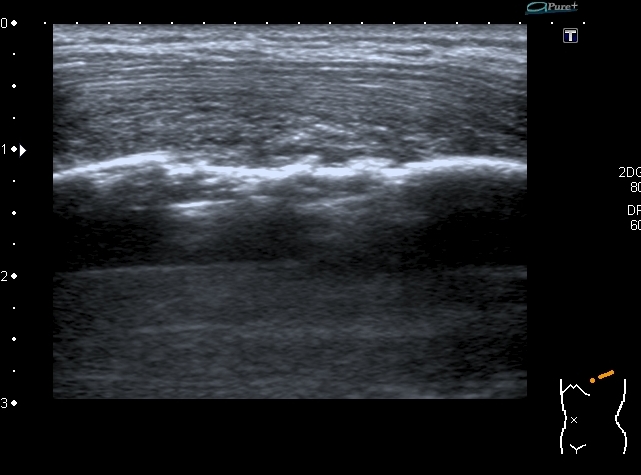

12-years old boy with torax palpable mass 5x3 cm.

Сегодня смотрел мальчика 12 лет, у которого на грудной клетке пальпируется опухоль около 5 см х3 см.

На УЗИ - такая картинка:

Деструкция корткального слоя 7-го ребра с ткаенвым компонетом, исходящим из кости. 7th rib destruction with solid mass

Поперечный скан. Transverse scan

образование оттесняет сосуд,  в самом кровоток достоверно не определяется. No bloodflow in mass is detected.